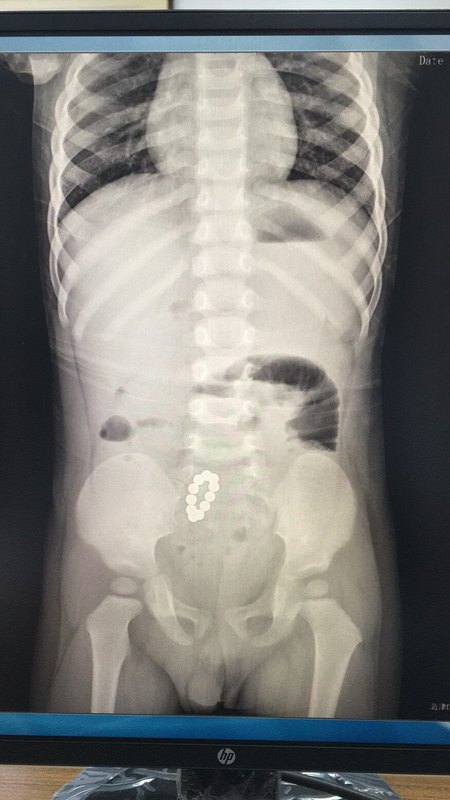

磁力珠,大危害

現(xiàn)在小朋友的玩具越發(fā)多樣性,只不過如有些玩具操作不當(dāng)?shù)脑挘瑫o小朋友帶來致命的傷害。近日,2歲大的小雨不知為何突然出現(xiàn)一陣陣腹痛,吃東西后腹痛更加明顯,當(dāng)時家里人還沒有重視,后來還伴有嘔吐,隨后小雨爸媽便帶他到東莞市兒童醫(yī)院就診,在門診拍片子發(fā)現(xiàn)小雨肚子里竟然有串珠樣的金屬異物,考慮磁力珠,立即轉(zhuǎn)入小兒外科治療,經(jīng)過外科醫(yī)師初步判斷異物是在小腸下段的位置。 考慮到小雨已出現(xiàn)嘔吐、腸管擴(kuò)張等腸梗阻的表現(xiàn),外科醫(yī)師立即安排了腹腔鏡手術(shù),在腹腔鏡中探查發(fā)現(xiàn),小雨腸管內(nèi)的一部分異物已經(jīng)穿出小腸,而且造成腸管粘連和多處穿孔 經(jīng)過清創(chuàng)、修補(bǔ)腸管以及腸系膜等,終于順利完成手術(shù),小雨也在小兒外科醫(yī)護(hù)團(tuán)隊(duì)的精心照顧下,身體逐漸康復(fù),順利出院。 磁力珠為何會導(dǎo)致穿孔呢?因?yàn)榇帕χ橛袕?qiáng)大的吸力,磁力珠彼此吸附,使腸管夾在磁力珠中間,使腸壁缺血壞死,從而導(dǎo)致腸穿孔。最后,告誡廣大家長,小小的磁力珠,危害卻十分大,這種危險玩具務(wù)必遠(yuǎn)離孩子,給孩子一個健康安全的成長環(huán)境。